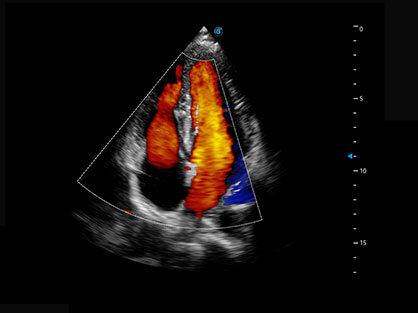

通过对组织运动信息、血流信号及背景噪声进行准确智能的阈值判定,高效提取出微弱血流信号,获得高灵敏度和空间分辨率的血流图像,为临床提供更加真实和丰富的诊断信息。

可同时显示组织结构表面和内部的轮廓信息,达到透视效果,为临床提供更丰富的诊断信息。